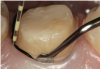

Tooth preparation should be performed as dictated by the type and substrate of the final restoration. Various types of restorations and substrates require different preparation methods. For example, lithium disilicate, porcelain-fused-to-metal (PFM), and porcelain-fused-to-zirconia (PFZ) anterior crown preparations require 1.5 to 2.0 mm incisally, 1.5 mm facially and lingually, and 1.0 mm at the cervical third facially and lingually. Full zirconia crowns in the posterior require 1.0 mm at the cusp tips, 1.5 mm occlusally, 1.0 mm buccally and lingually, and .75 mm at the marginal areas (gingival third of the tooth). Lithium disilicate, PFM, and PFZ posterior crowns require 1.5 to 2.0 mm occlusally, 1.5 mm buccally and lingually, and 1.0 mm at the gingival third or at the margin area (Figure 2).

Fig 2. Different restorations and substrates require different preparation measurements.

Figure 2